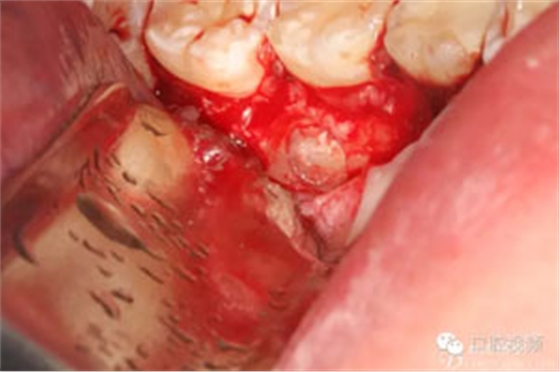

圖8.繼續(xù)去骨、暴露整個(gè)35牙冠。注意牽拉力度。